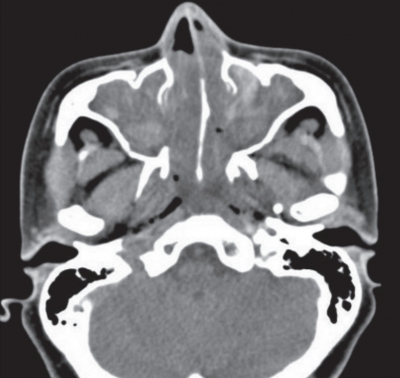

48 歳の女性。鼻閉を主訴に来院した。数年前から鼻閉と嗅覚低下があり、風邪をひくと悪化した。鎮痛薬で気管支喘息を起こしたことがあった。左鼻腔の内視鏡像を別に示す。右鼻腔も同様の所見である。副鼻腔単純 CT の水平断像と冠状断像を別に示す。

慢性副鼻腔炎の症例。

内視鏡下鼻副鼻腔手術は、慢性副鼻腔炎や鼻茸に対して広く行われる治療法で、症状の改善と機能の回復を目的としている。

内視鏡を使用することで副鼻腔内の病変に直接アクセスし、鼻茸の除去や排液の改善を行う。